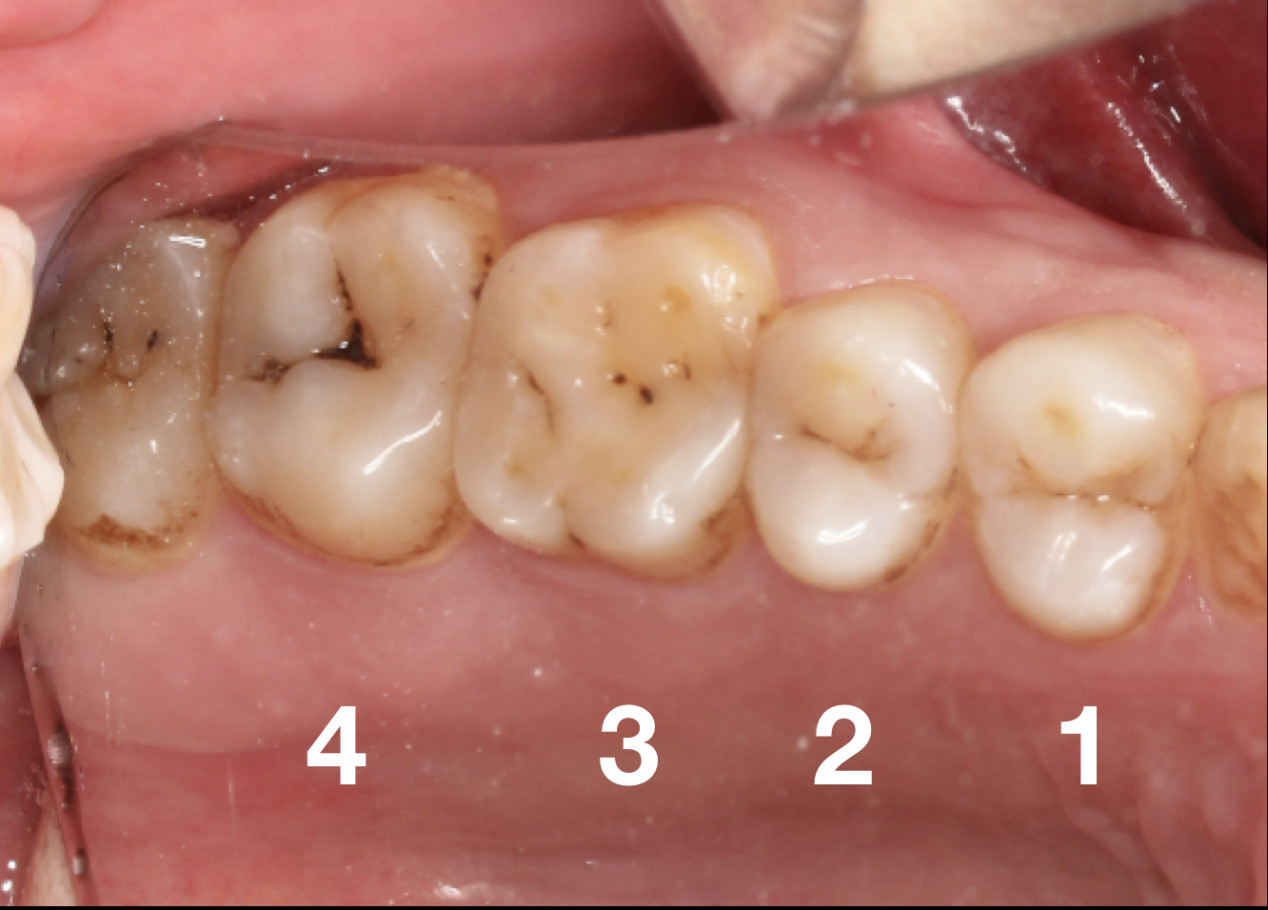

初期我们很难发现被细菌“盯”上的牙齿,等牙疼了才能明白,原来小黑线、黑块是龋齿(蛀牙)的表现。

想要知道到底是龋齿,还是色素沉着,还是比较难分辨的。但色素沉着一般会导致多颗牙齿被染色,染色是比较均匀的。

而蛀牙一般只有一两颗牙齿会显示出黑线。但是当色素牙和蛀牙同时出现时,我们就很难辨别出来了,只能通过医疗设备X-光检查。

牙齿龋坏疼痛发展过程

浅龋。牙齿表面有黑线,最表层牙釉质被破坏,初步形成蛀牙。

中龋。龋坏加重,牙齿第二层牙本质被破坏。遇冷热酸甜食物牙齿会敏感,冷刺激尤为明显,可出现疼痛反应,当刺激源去除后疼痛立即消失。

深龋。龋坏到达牙本质深层,一般表现为大而深的龋洞,或入口小而深层有较为广泛的破坏。对外界刺激反应比中龋重,但刺激源去除后,仍可立即止痛,无自发性痛。